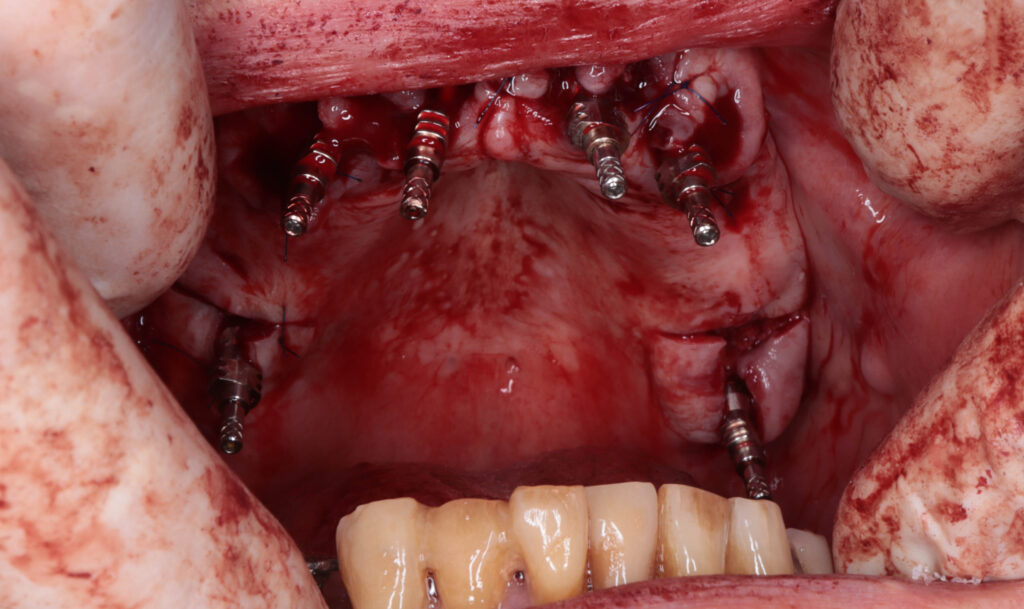

Процесс работы

Что было сделано:

На верхней челюсти была проведена комплексная имплантация по системе All-on-4,

установлены 4 имплантата Megagen AnyOne.

Спустя 7 дней на верхней челюсти зафиксирован металлоакриловый протез из 12 зубов.

пациент по время имплантации

Это фото может содержать тяжелый для восприятия контент